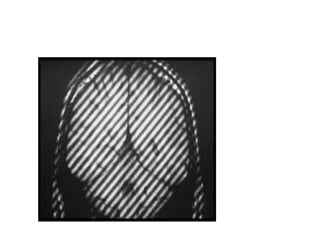

Crisscross or Herringbone Artifacts

• caused

due to a data processing or

reconstruction error.

• Appears

It is characterized by an obliquely oriented

stripe that is seen

throughout the image.

• Eliminated

reconstructing the image again.

Crisscross or HerringboneArtifacts • caused due to a data processing or reconstruction error. • Appears It is characterized by an obliquely oriented stripe that is seen throughout the image. • Eliminated reconstructing the image again.